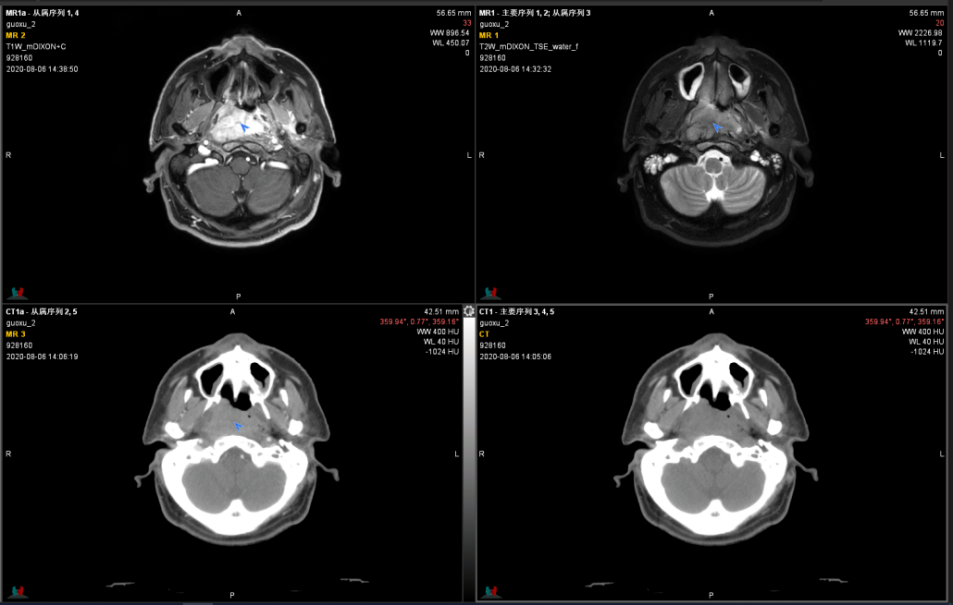

图2-3为一鼻咽癌患者MR-CT融合定位 3D扫描,其鼻咽部病灶在MR上肿瘤边界清晰,在勾画靶区过程中MR的增强、CT平扫、CT增强融合配准后3维立体同步联动,大大提高了靶区的精准性。

图2鼻咽癌MR vs CT

图3MR-CT融合定位3维立体定位肿瘤